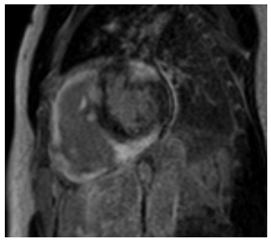

On CMR SSFP, better quantification of LV and papillary muscle mass can be made and tracked over time compared to echocardiography. Glycosphingolipid accumulation in myocytes results in a shorter T1 relaxation time on the T1 mapping sequence. In a systemic review, the mean T1 value in FD patients was 935 +/− 48 ms with a 1.5 T CMR scanner, compared to 999 + 31 ms in controls []. Shortened native T1 time has been described in individuals with FD without LVH and correlates with a reduced GLS on echocardiography []. Pseudo-normalization of native T1 time can be noted in areas of myocardial fibrosis or inflammation []. Native T2 mapping can show elevated T2 relaxation time in the basal inferolateral region or other areas of LGE, which reflects myocardial inflammation []. Post-contrast imaging would classically show a pattern of LGE involving the mid-myocardium of the basal inferolateral wall. However, LGE may become more extensive in advanced cases []. ECV values are normal in FD but may increase in areas of fibrosis. Key CMR findings in Fabry disease are summarized in Table 2.

4.5. The Role of CMR in Prognosis and Disease Monitoring

CMR can risk stratify patients with FD cardiomyopathy and provide prognostic value. For instance, higher LV mass index and more extensive LGE are strongly correlated with the incidence of cardiovascular events, including heart failure, arrhythmias, and cardiac death []. Lower native T1 time is also prognostic as it reflects Gb3 accumulation. Orsborne et al. included age, LV mass index, and native T1 time in a prognostic model that estimates the 5-year risk of adverse cardiovascular events [].

CMR is used to monitor the response to therapy for FD. The response of LVH to therapy has been shown to be variable, with patients with baseline LVH and minimal LGE having more reduction []. T2 time reduces with successful treatment. T1 time would be expected to normalize with therapy as well, however, there have not been studies demonstrating the utility of monitoring T1 time with therapy []. Expert groups suggest routinely obtaining CMR every 2–5 years before the onset of cardiac features and then every 2–3 years in patients with progressive disease to monitor the progression of FD cardiomyopathy and evaluate the success of therapy [,,].